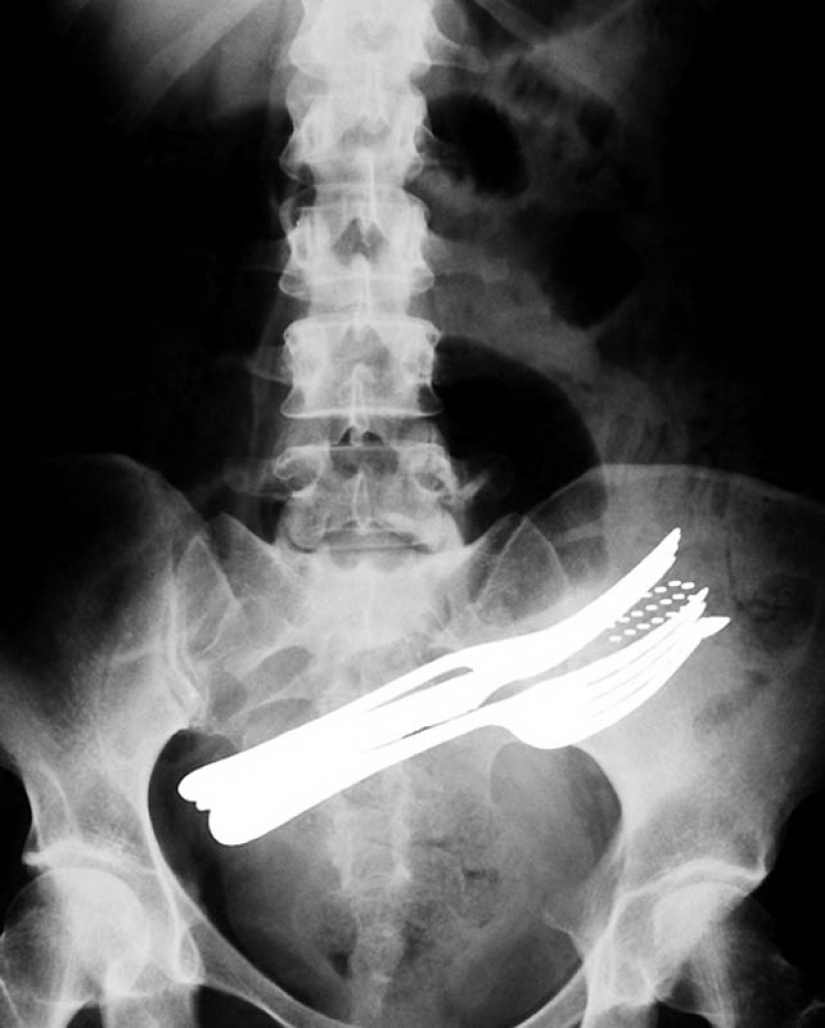

2. The stomach of a patient who swallowed two forks, a ballpoint pen and a toothbrush.